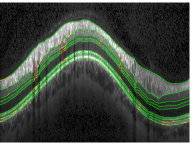

Average boundary-wise results are summarized in Table 2. In general, boundaries 1 and 6 to 9 turned out to be easier to segment than boundaries 2 to 5. For boundary 1 this stems from easily detectable textures, whereas boundaries 6-9 with their regular shape profit disproportionately from regularization by the shape prior. Boundaries 2-5 on the other hand pose a harder challenge with their high variability of texture and shape. The upper row in Fig. 9 shows an example close to the average segmentation performance with Eunsgn=2.97μmsubscript𝐸unsgn2.97𝜇𝑚E_{\mathrm{unsgn}}=2.97\,\mu m.

Refer to caption

(a)

(b)

(c)

(d)

Figure 9: Top: Segmentation (Eunsgn=2.97μmsubscript𝐸unsgn2.97𝜇𝑚E_{\mathrm{unsgn}}=2.97\,\mu m) of a non-pathological circular scan. Bottom: Segmentation (Eunsgn=5.09μmsubscript𝐸unsgn5.09𝜇𝑚E_{\mathrm{unsgn}}=5.09\,\mu m) of an advanced glaucomatous scan.

For the pathological scans segmentation performance was comparable to the healthy scans, but decreased with the progression of the disease. This happened for two reasons: Since glaucoma is known to cause a thinning of the nerve fiber layer (NFL) Schuman et al. (1995); Bowd et al. (2001), the shape prior trained on healthy scans may encounter difficulties adapting to very abnormal glaucomatous shapes. Furthermore, we observed a reduced scan quality for glaucomatous scans, also reported by others Ishikawa et al. (2005); Stein et al. (2006); Mayer et al. (2010), which in turn reduced the quality of the data terms. For advanced primary open-angle glaucoma, the NFL can even vanish at some locations. The appearance model for this layer, trained on healthy data, is not able to detect these extreme anomalies, which resulted in a comparatively low performance for some scans. We discuss possible modifications to overcome this problem in Section 7.

The bottom panels in Fig. 9 show an example of a PGA-type scan and its segmentation. The scan exhibits the discussed reduced scan quality. Furthermore, the segmentation proves that the shape model can generalize well to pathological shapes as well as scan artifacts.